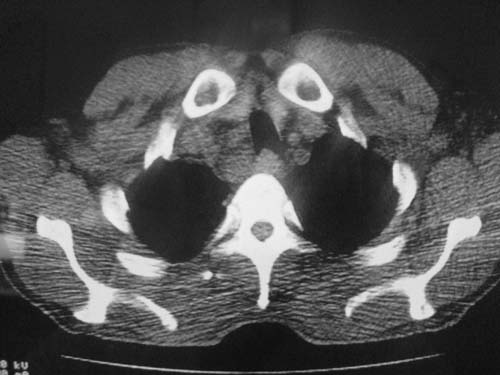

以下是引用科室第一人在2010-3-25 20:30:00的发言:[br]1:纵膈肿瘤性病变,恶性胸腺瘤可能性大伴纵膈右肺门淋巴结转移,右侧胸腔积液。[br]2:右侧肺门肿瘤性病变,纵膈淋巴结转移,右侧胸腔积液。右下叶转移。

以下是引用子期在2010-3-25 21:00:00的发言:[br]先考虑右中央型肺癌伴转移。

以下是引用江广1996在2010-3-25 22:49:00的发言:[br]通常肺癌向纵隔转移多见,纵隔肿瘤向肺内转移少见(有的表现为向肺内侵润)。本例以一元论考虑:右中心型肺癌并纵隔淋巴等多处转移。[br][br][本贴已被 江广1996 于 2010-3-25 22:50:07 修改过]

以下是引用yangyudong333在2010-3-26 6:43:00的发言:[br]“冰冻纵膈”,考虑纵膈淋巴瘤伴肺内及胸膜侵润。